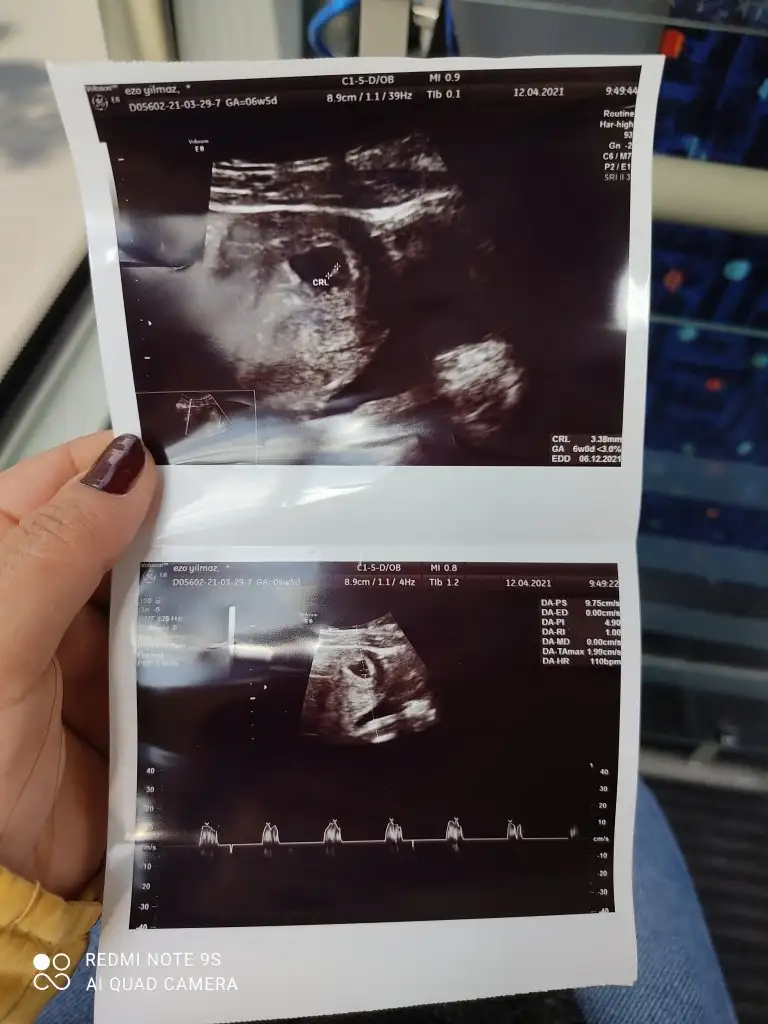

Cinsiyetini öğrendiniz miEki Görüntüle 2777702 Eki Görüntüle 2777703 Eki Görüntüle 2777704 6+4 7+4 11+4 yorumlayabilir misiniz? Henüz belli olmadı cinsiyetimiz